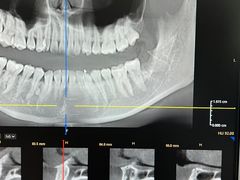

• 牙博士口腔品牌连锁(杨浦店)

• -牙博士口腔品牌连锁(杨浦店)

郑杰 | 24-02-02